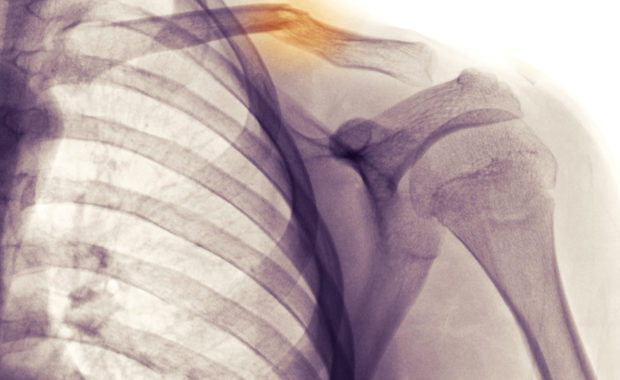

Physical Therapy For Collarbone Fractures

Your collarbone plays a pivotal role in stabilizing your shoulder and arm, but it’s also not the best suited to handle trauma. Because of this, it’s